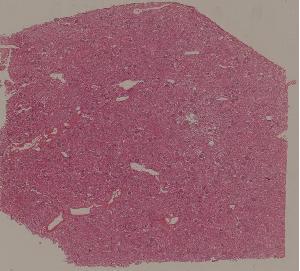

低倍视野

68. Biliary fibrosis

69. Hepatocellular carcinoma